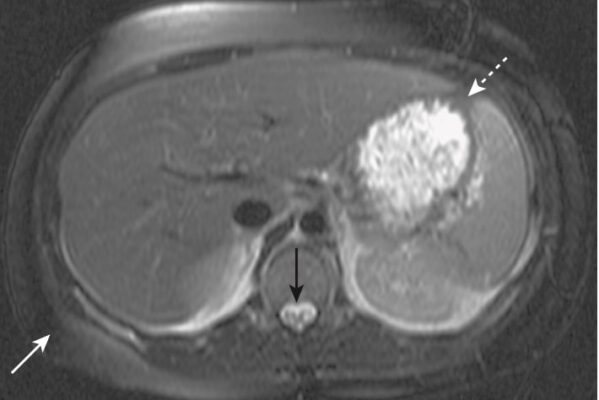

- Các cấu trúc trở nên sáng trên hình ảnh hậu gadolinium thường là mạch máu (chẳng hạn như khối u) (Hình 11) hoặc các mô bị viêm, và được mô tả là tăng cường (enhancing).

| Tiêu hoá | Gan Đường mật Ruột non và ruột già | Làm rõ đặc tính tổn thương gan; phát hiện các tổn thương nhỏ; nang; ung thư tế bào gan; quá sản nốt khu trú; hemochromatosis (rối loạn sắc tố di truyền); thâm nhiễm mỡ Chụp đường mật tuỵ cộng hưởng từ với chít hẹp, giãn Chụp ruột cộng hưởng từ; viêm ruột thừa ở phụ nữ có thai |